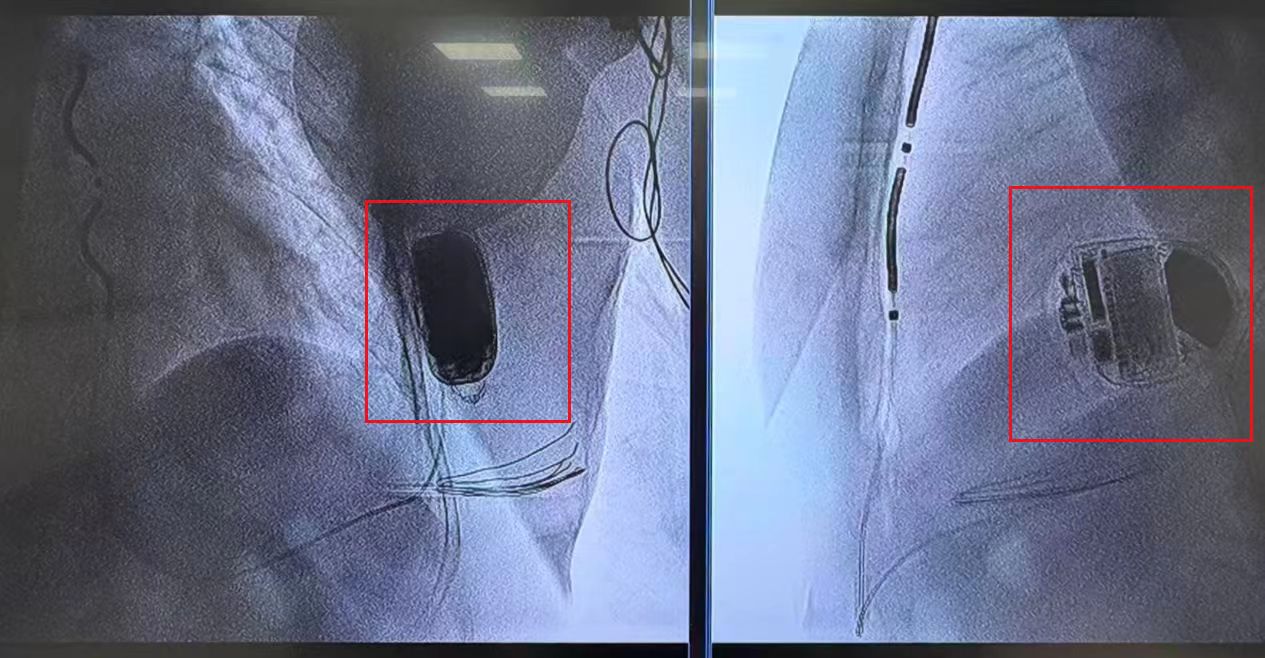

头图中红框处为胡阿姨植入最新型2.0版血管外植入式除颤器。胸科医院供图

这个最新型除颤器,从逻辑上属于“血管外除颤器”,但和传统相比,新型技术发生了升级,医生们会将除颤器的电极隐藏在胸骨和心脏中间,像“创可贴”一样覆盖在心脏表面,这样,既解决了血管受损问题,也因缩短距离,大大提升了除颤器的能量作用。2.0版的除颤做到了一举两得!它已在2025年6月经国家药品监督管理局获批上市,是目前全球最新的植入式除颤系统。

为了确保手术安全,在植入术前,心内科不仅规划了电极植入路径,还和心外科专家、麻醉医师共同讨论手术操作细节,对术中可能遇到的问题进行了充分的讨论和准备。植入手术过程顺利,植入的胸骨下电极稳定,电学参数正常,除颤测试通过。经过一夜监测后,胡阿姨术后第一天就转回普通病房,目前恢复良好。